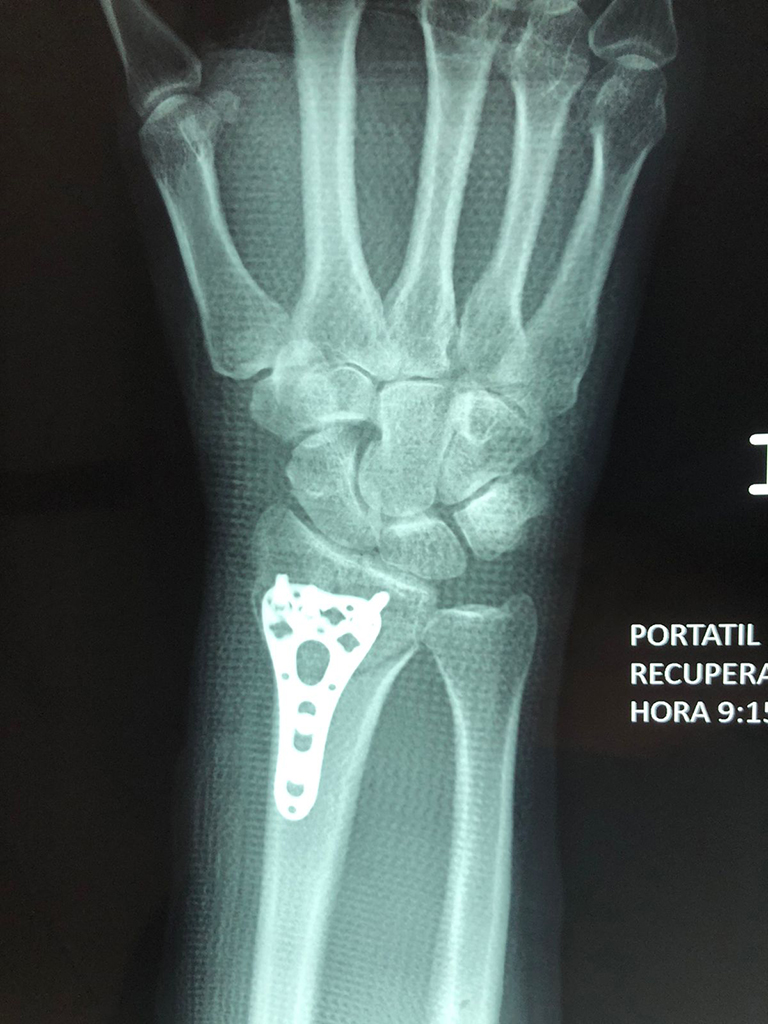

Cirugías de Muñecas

Los procedimientos más comunes en cirugía de la mano son aquellos destinados a reparar traumatismos, incluyendo lesiones de tendones, nervios, vasos sanguíneos, y articulaciones; huesos fracturados; y quemaduras, cortes, y otros daños de la piel.